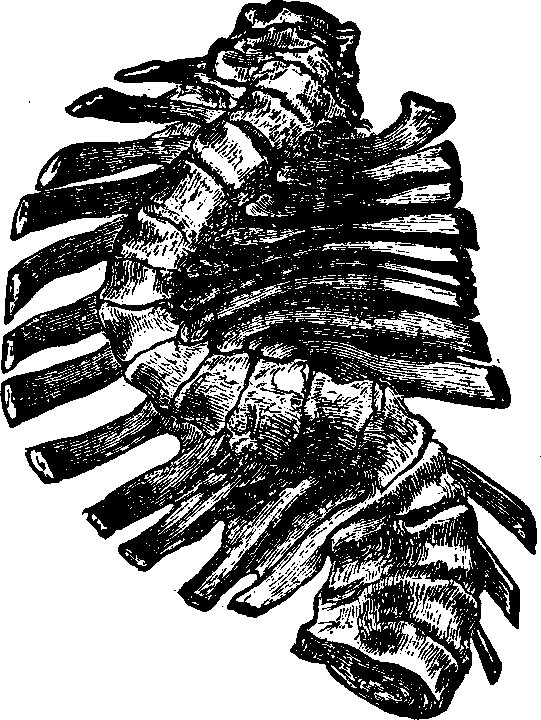

In the membranous variety of dysmenorrhea, the entire mucous membrane which lines the cavity of the uterus, in consequence of some morbid process, is gradually detached and expelled at the menstrual period.

Symptoms. There are steady pains at the commencement of the menstrual flow, and they increase in violence and become decidedly expulsive. The mouth of the uterus gradually dilates, and finally, the membrane is forced out of the uterus, attended with a slight flow of blood and an entire subsidence of the pain.

The treatment, in all the preceding varieties of dysmenorrhea, should consist of measures to determine the circulation of the blood to the surface, and increase the perspiratory functions. Congestion and inflammation of the internal organs are generally induced by exposure to cold or from insufficient clothing. Sometimes they follow from neglect of the skin, which is not kept clean and its excretory function encouraged by warm clothing. The domestic treatment at the monthly crisis should be commenced by the administration of hot foot, and sitz-baths, after which the patient should be warmly covered in bed, and bottles of hot water applied to the extremities, back, and thighs. Dr. Pierce's Compound Extract of Smart-weed should be given in full doses, frequently repeated, to secure its diaphoretic, emmenagogue, and anodyne effects, which, for this painful affection, is unsurpassed. For the radical cure of this disease, whether of a congestive, inflammatory, or neuralgic character, Dr. Pierce's Favorite Prescription, which is sold by druggists, is a pleasant and specific remedy, which will most speedily correct the abnormal condition that produces the trouble, and thereby obviate the necessity of passing this terrible [pg 694]ordeal at every monthly period. The patient should take two teaspoonfuls of the medicine three times a day, and keep up its use in these doses for weeks. Frequently, one month will suffice to cure, but in most cases, a longer season is required. In the end, the suffering patient will not be disappointed, but will become a new being, ready for the enjoyment and duties of life. The bowels should be kept regular throughout the treatment by the use of Dr. Pierce's Pleasant Pellets, if necessary. A hand or sponge-bath should be used daily to keep the skin active, and be followed by a brisk rubbing of the surface with a rough towel or flesh-brush. A wet sheet pack will cleanse the pores of the skin and invite the blood into the minute capillaries of the surface, and thus prove of great benefit. It should be repeated after an interval of seven days, but ought to be omitted if near the approach of a menstrual period. The clothing should be warm, to protect the system against changes of temperature; especially should every precaution be taken to keep the feet dry and warm. The patient should walk in the open air, and the distance should be regularly lengthened at each succeeding walk. If the course of treatment which we have suggested be faithfully pursued, a permanent cure will be effected.

In the obstructive variety of dysmenorrhea, some organic impediment hinders the exit of the menstrual blood from the uterus, which, consequently, becomes distended and painful. The pain may be constant, but is most acute when the uterus makes spasmodic efforts to discharge the menstrual blood. If these efforts prove successful, there is an interval of relief. Flexion or version of the womb may produce partial occlusion of the canal of the neck of the uterus, thus preventing the free flow of the menstrual fluid through it. Tumors located in the body or neck of the uterus often cause obstruction to the free discharge of the menses. Imperforate hymen and vaginal stricture also sometimes cause obstruction and give rise to painful menstruation. As these several abnormal conditions and diseases will be treated of elsewhere in this volume, we omit their further consideration here.